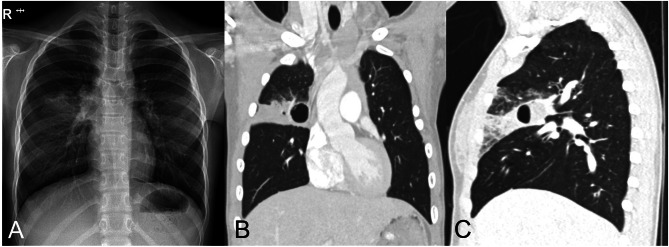

A 10-year-old girl visited the Department of Otolaryngology as an outpatient, having sensed a mass/swelling on the left floor of mouth for 2 weeks. A history of bronchopulmonary dysplasia (BPD), linked to very low preterm birthweight, was acknowledged. There was a cystic lesion on floor of mouth, confirmed by computed tomography (CT) of the neck. The cyst (1.5 × 3.9 cm) occupied left anterior sublingual space, but a right hilar cystic lung lesion (2.3 × 1.5 cm) was also identified. She was referred to our Department of Thoracic and Cardiovascular Surgery to manage the lung lesion. On physical examination, the patient was asymptomatic and otherwise sound. Blood culture, oral culture, and urine culture were performed, and there was no growth of microorganisms. Therefore, no adjunctive antibiotics were administered. Chest X-ray again disclosed a cystic lesion and consolidation within right hilar region (Fig. 1A). CT of the chest further defined the consolidation, situated in anterior segment of right upper lobe (RUL) and harboring an internal cystic space (2.4 cm) with air-fluid level. Overall findings suggested a congenital cystic growth complicated by pneumonia (Fig. 1B, C).

Fig. 1.

Preoperative imaging studies: (A) chest X-ray demonstrating cystic lesion and consolidation in right hilar area and (B, C) computed tomography of chest (coronal and sagittal views) with similar findings confined to anterior segment